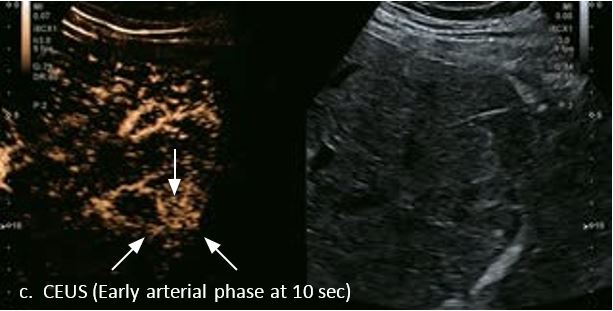

LI-RADS 4 множинні ГЦК

Це випадок 60-річної жінки з декомпенсованим цирозом печінки з асцитом. На сірошкальному зображенні можна виявити два вогнищевих ураження, розміром 21 мм і 10 мм відповідно, розташовані в сегменті 5. Оскільки дослідження методом зсувної хвилі на апараті Canon виконується штовхаючим імпульсом, пацієнтам з асцитом не можна проводити дослідження за допомогою зсувної хвилі, для визначення стадії фіброзу. На ранній артеріальній стадії гомогенне гіперехогенне підсилення спостерігається в обох ураженнях. Ураження є ізоехогенними в портальній венозній та пізній фазах, вимивання не спостерігається через 6 хвилин після ін'єкції, тому ці ураження були класифіковані як LI-RADS 4, ймовірна ГЦК. Важливо знати, що LI-RADS 5 - це ГЦК зі 100% вірогідністю, і вона не потребує біопсії. Значна кількість LI-RADS M (ймовірно або точно злоякісні, але не специфічні для ГЦК) і LI-RADS 4 (ймовірна ГЦК) насправді являються ГЦК.

Малюнок 11